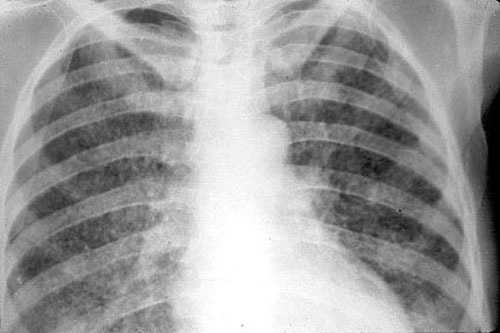

Рентген

Опасным воспалением при туберкулезе или пневмонии считается верхнедолевой очаг поражения, который чаще всего поражается микобактериями.

При пневмонии обнаруживаются на рентгене изменения, позволяющие отличить ее от туберкулеза:

- Уплотнение (инфильтрация) участка легких с неявными, размытыми очертаниями или в виде дымки (характерно для снимков при острой форме).

- Усиление легочного рисунка (при интерстициальной форме).

При верхнедолевой левосторонней пневмонии поражается до 5 долей легкого. Заболевания этого органа протекают тяжелее, чем правосторонняя пневмония, при которой поражается 1-3 участка.

Флюорографией при пневмонии чаще выявляется поражение нижних и средних частей с изменениями корня легкого.

При туберкулезном инфицировании изменения отмечаются в верхней части легкого, отличаются четкими очертаниями, без видимых изменений корня.

На рентгенограмме обнаруживается при туберкулезе:

- Диссеминированном. Множество мелких, хорошо очерченных, или более крупных пятен, есть каверны.

- Очаговом. Уплотнение находится не ниже 2 ребра, вокруг могут быть фиброзные тяжи, усилен легочный рисунок.

- Инфильтративном. Уплотнения правильной округлой формы на рентгеновском снимке в верхней легочной доле.

- Казеозной пневмонии. Множество полостей распада с неровными краями, очагами отсева, смещением средостения в больную сторону груди.

Рентгеновские снимки на сегодняшний день являются самым надежным методом в постановке диагноза заболеваний легких. Их поражение присутствует в обоих случаях, однако картина существенно различается.

Рассмотрим основные отличия этих заболеваний на снимках:

- Локализация поражений легочной ткани. При пневмонии инфильтративные тени, характеризующие очаги поражения, просматриваются, как правило, в 3, 4, 5, 7, 8, 9 долях легкого, преимущественно поражая нижние участки. Туберкулез, в свою очередь, имеет одностороннюю локализацию, в большинстве случаев поражая правую долю легких в 1, 2, 6 сегментах.

- Очертания теней. При пневмонии инфильтраты (рентгеновские тени) имеют размытые, нечеткие очертания. В острый период заболевания затемнение напоминает дымку, а по мере развития воспаления интенсивность теней возрастает, но нечеткий характер краев сохраняется. Туберкулез же имеет тени с выраженным четким рисунком.

Форма теней. Очаги поражения при пневмонии, как правило, округлой, неправильной, кольцевидной или веретенообразной формы. Площадь поражения зависит от формы заболевания:

- очаговые тени имеют белый цвет и в диаметре не превышают полутора сантиметров, бывают в начале заболевания или при выздоровлении,

- долевая форма характеризуется полным поражением доли легкого,

- сегментарные тени – инфильтрация определенного сегмента,

- крупозная форма – самый тяжелый вариант, при котором воспаляются оба легких, сопровождается различными множественными очагами теней с обеих сторон органов.

Инфильтраты при туберкулезе зависят от формы данного заболевания:

- Диссеминированный туберкулез сопровождается множественными мелкими очагами до 2 мм в диаметре,

- Очаговый , имеет один или несколько теней округлой, эллиптической, реже вытянутой формы с низкой интенсивностью, при которой очаги поражений темнее костной ткани,

- Казеозная форма является самой тяжелой и сопровождается затемнением нескольких долей или даже целого легкого, тень изменяется по мере распада от менее интенсивной до более выраженной,

- Кавернозный , характеризуется очаговым затемнением с просветом посередине (каверна).

Рентгеновские снимки может верно интерпретировать только специалист, имеющий опыт работы в данной области.